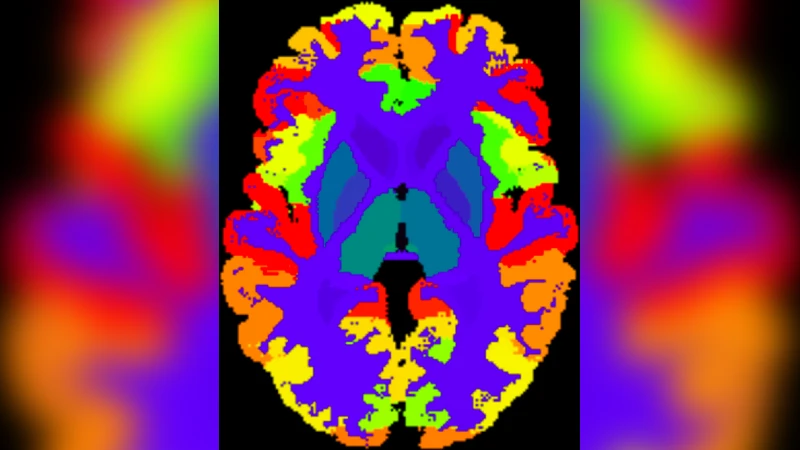

AssemblyNet: A Novel Deep Decision-Making Process for Whole Brain MRI Segmentation

Whole brain segmentation using deep learning (DL) is a very challenging task since the number of anatomical labels is very high compared to the number of available training images. To address this problem, previous DL methods proposed to use a global convolution neural network (CNN) or few independent CNNs. In this paper, we present a novel ensemble method based on a large number of CNNs processing different overlapping brain areas. Inspired by parliamentary decision-making systems, we propose a framework called AssemblyNet, made of two “assemblies” of U-Nets. Such a parliamentary system is capable of dealing with complex decisions and reaching a consensus quickly. AssemblyNet introduces sharing of knowledge among neighboring U-Nets, an “amendment” procedure made by the second assembly at higher-resolution to refine the decision taken by the first one, and a final decision obtained by majority voting. When using the same 45 training images, AssemblyNet outperforms global U-Net by 28% in terms of the Dice metric, patch-based joint label fusion by 15% and SLANT-27 by 10%. Finally, AssemblyNet demonstrates high capacity to deal with limited training data to achieve whole brain segmentation in practical training and testing times.

This paper tackles the notoriously difficult problem of whole‑brain MRI segmentation, where the number of anatomical labels (132) far exceeds the number of available manually annotated training scans. While previous deep learning approaches have relied on a single global 3D U‑Net, patch‑wise networks, or the SLANT framework that splits the brain into a modest number of overlapping sub‑volumes (e.g., 8 or 27), these methods either struggle with limited data or require extensive computational resources.

Experimental results demonstrate that AssemblyNet, using only the 45 training images, achieves a mean Dice coefficient of 73.3 % on 19 test scans (132 labels). This outperforms a global U‑Net (57.0 % Dice, +28 %), SLANT‑8 (57.0 %, +28 %), SLANT‑27 (66.1 %, +10 %), and the classic patch‑based Joint Label Fusion (63.4 %). The coarse‑only assembly (2 mm) already reaches 67.9 % Dice; adding the multiscale cascade improves performance by 1.6 % absolute Dice. Training time is about 7 days and inference takes roughly 10 minutes per scan, comparable to SLANT‑27 but without the massive library extension (which would require 21 CPU‑years for 5 111 auxiliary scans).

Performance is further analysed across three test cohorts: adult OASIS scans, pediatric CANDI scans, and the high‑resolution Colin27 scan. AssemblyNet consistently yields the highest Dice scores (78.8 % on OASIS, 71.1 % on CANDI, 74.2 % on Colin27), demonstrating robustness to different acquisition protocols and age groups. Notably, while other methods suffer a dramatic drop on the pediatric data, AssemblyNet maintains strong performance, highlighting the benefit of knowledge sharing and atlas priors in handling distribution shifts.